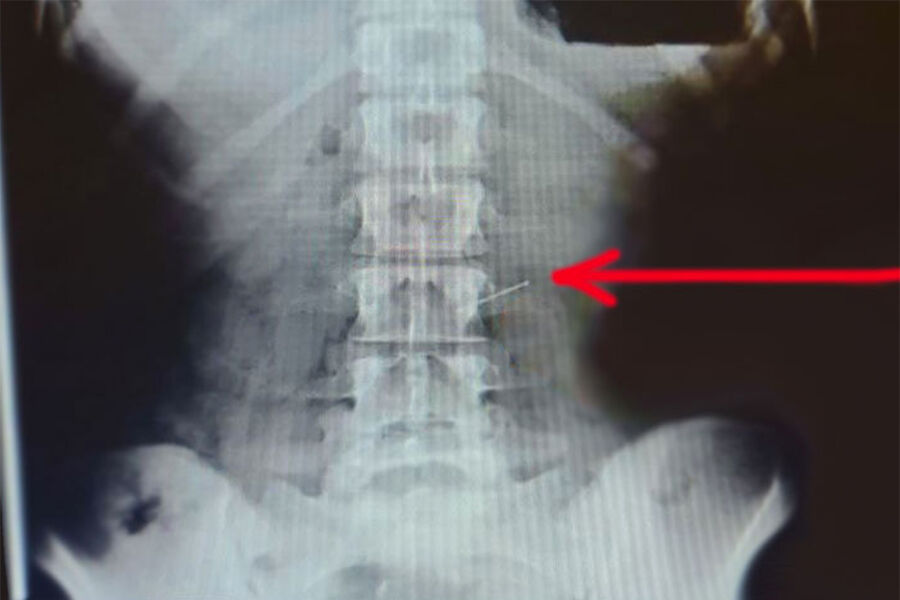

В Московской области врачам удалось спасти 30-летнюю местную жительницу, которая проглотила портновскую булавку. Об этом сообщает пресс-служба больницы им. Розанова.

Инцидент произошел в Пушкино. Во время работы женщина захватила губами портновскую булавку, после чего вдохнула — острый инородный предмет попал в горло, а дальше во внутренние органы. В больнице было установлено, что игла находилась в желудке.

Хирургам потребовалось около часа, чтобы специальным зажимом «поймать» булавку и достать, не повредив при этом желудок и стенки пищевода.